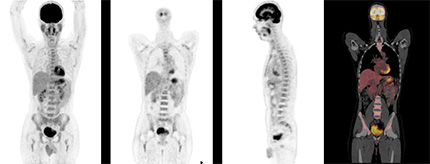

2018年4月より、川崎市立川崎病院にPET-CTが導入されました。これまで、川崎市内のPET-CT施設は北部地域の1施設のみでしたので、南部地域としては初となります。これからは地域の皆さまが遠方の医療機関まで足を運ぶことなく、川崎病院でPET-CT検査を受けていただくことができます。また、地域の医療機関にもPET-CT装置を共同利用していただくことにより、より一層の連携強化と信頼される医療の提供を目指してまいります。

この装置には、高性能な検出器及び最新の撮像技術が搭載されており、高画質の画像データを短時間で収集することが可能です。これにより、患者さんの負担を大きく軽減することができます。

PET-CT検査で使われる18F-FDG(フルデオキシグルコース)は、放射性核種のフッ素(18F)で標識された、ブドウ糖によく似た構造の薬剤です。脳や心臓は、ブドウ糖を使って活動するため、大量のブドウ糖を取り込みます。また、がん細胞は糖代謝が活発なため、正常な細胞の3から8倍ものブドウ糖を取り込みます。全身のブドウ糖が取り込まれる様子を観察できることから、脳や心臓、がんなどの病気の診断に有用です。